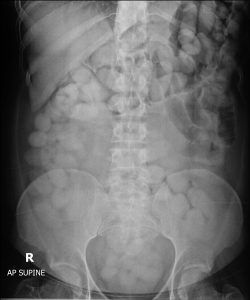

สำหรับการตรวจพบการกระทำความผิดตามกฎหมายศุลกากรประจำเดือนมิถุนายน 2565 มีจำนวน 3,068 คดี คิดเป็นมูลค่ารวม 227.24 ล้านบาท มีผลงานที่น่าสนใจ ดังนี้ 1. ผลการจับกุมยาเสพติด 1.1 เมื่อวันที่ 9 มิถุนายน 2565 ด่านศุลกากรท่าอากาศยานภูเก็ต ตรวจค้นสัมภาระผู้โดยสารที่เดินทางมาจากต่างประเทศ เบื้องต้นไม่พบสิ่งผิดกฎหมายแต่มีข้อพิรุธที่อาจจะลักลอบกลืนยาเสพติด จึงนำตัวไปเอกซเรย์ร่างกายที่โรงพยาบาลถลาง จังหวัดภูเก็ต จากการตรวจสอบภาพเอกซเรย์ พบสิ่งแปลกปลอมรูปร่างทรงกลมและทรงรีเป็นจำนวนมากในช่องท้อง ผลการตรวจสอบสิ่งแปลกปลอมดังกล่าว พบเป็นยาเสพติดให้โทษประเภท 2 โคคาอีน จำนวนรวม 115 ก้อน น้ำหนักรวมสิ่งห่อหุ้ม 1.49 กิโลกรัม มูลค่า 4.47 ล้านบาท 1.2 เมื่อวันที่ 13 มิถุนายน 2565 สำนักงานศุลกากรตรวจของผู้โดยสารท่าอากาศยานสุวรรณภูมิ ร่วมกับชุดปฏิบัติการ Airport Interdiction Task Force (AITF) ได้ทำการตรวจค้นกระเป๋าผู้โดยสารที่เดินทางมาจากต่างประเทศจำนวน 3 ราย พบหีบห่อต้องสงสัยภายในเป็นผงละเอียดสีขาว เมื่อทดสอบด้วยน้ำยาทดสอบเบื้องต้น พบเป็นสารเสพติดประเภทโคคาอีน จำนวนรวมทั้งสิ้น 15.7 กิโลกรัม มูลค่ารวม 47 ล้านบาท 1.3 เมื่อวันที่ 24 มิถุนายน 2565 กองสืบสวนและปราบปราม พบยาเสพติด ประเภทแมทแอมเฟตามีนซุกซ่อนในถุงข้าวสารส่งไปรษณีย์ออกนอกประเทศ ปริมาณ 2.96 กิโลกรัม มูลค่า 1.77 ล้านบาท อันเป็นการส่งของต้องห้ามต้องกำกัดส่งออกนอกราชอาณาจักร ตาม พ.ร.บ. ยาเสพติดให้โทษ พ.ศ. 2522 และพ.ร.บ. ศุลกากร พ.ศ. 2560